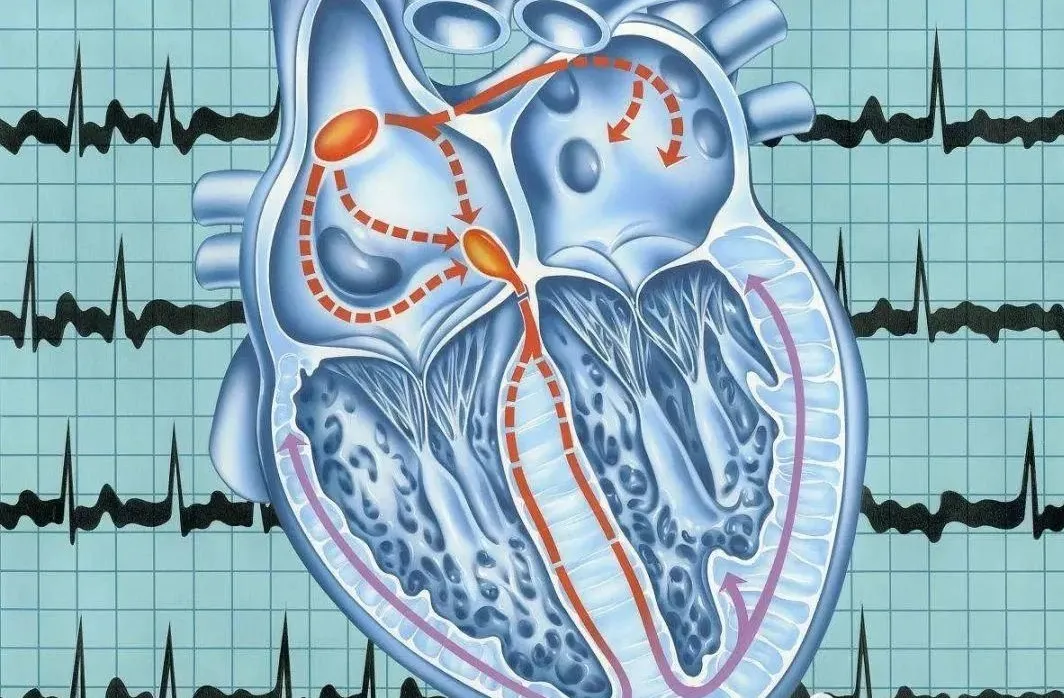

心房颤动

心房颤动也就是“房颤”,是最常见心律失常之一,可表现为阵发性发作,也可持续。

可以理解为心脏不规律的乱跳,正常人的心跳的节奏平缓,大概60次~100次/分钟,房颤的人心房频率可达到300~600次/分钟,而且很不规律。少数患者无明显症状,仅有心悸、胸闷、心慌;个别严重者头晕、晕厥。

房颤为什么会导致血栓栓塞和卒中?

房颤发生时可使心脏内的血流速度减慢,甚至还有可能停止,血液易在左心房的左心耳部位滞留,从而形成血栓,血栓脱落后可随血流入动脉,引发血栓栓塞事件,若血栓流入脑动脉则可造成脑血管阻塞而导致缺血性卒中。